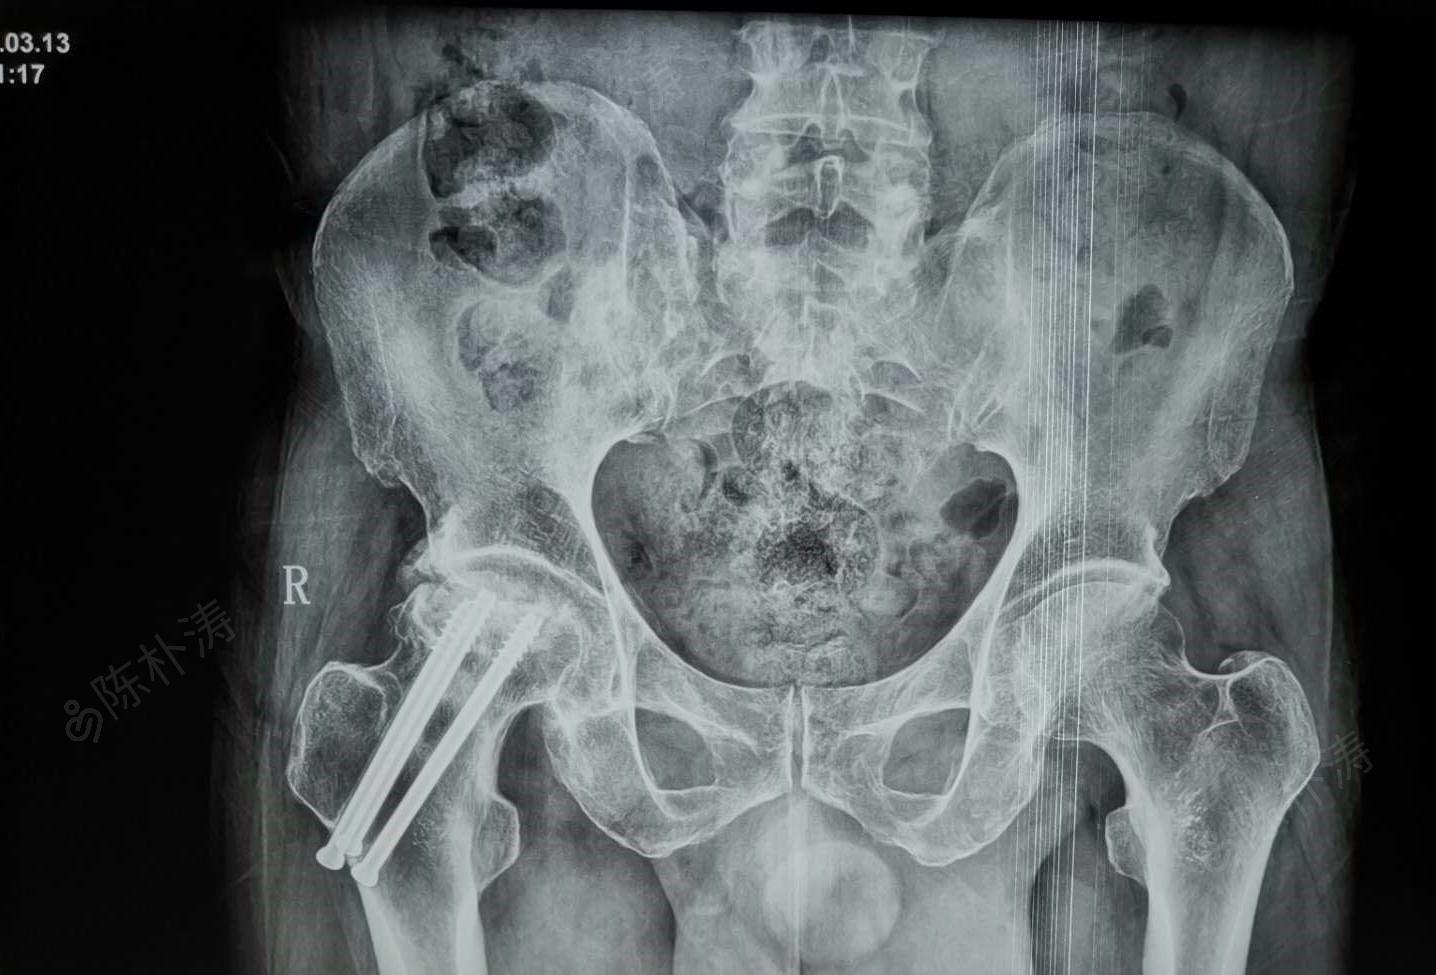

股骨颈骨折术后股骨头坏死

入院诊断:双侧股骨头坏死.

3.复杂股骨头坏死患者手术纪实,双市人民医院骨一科